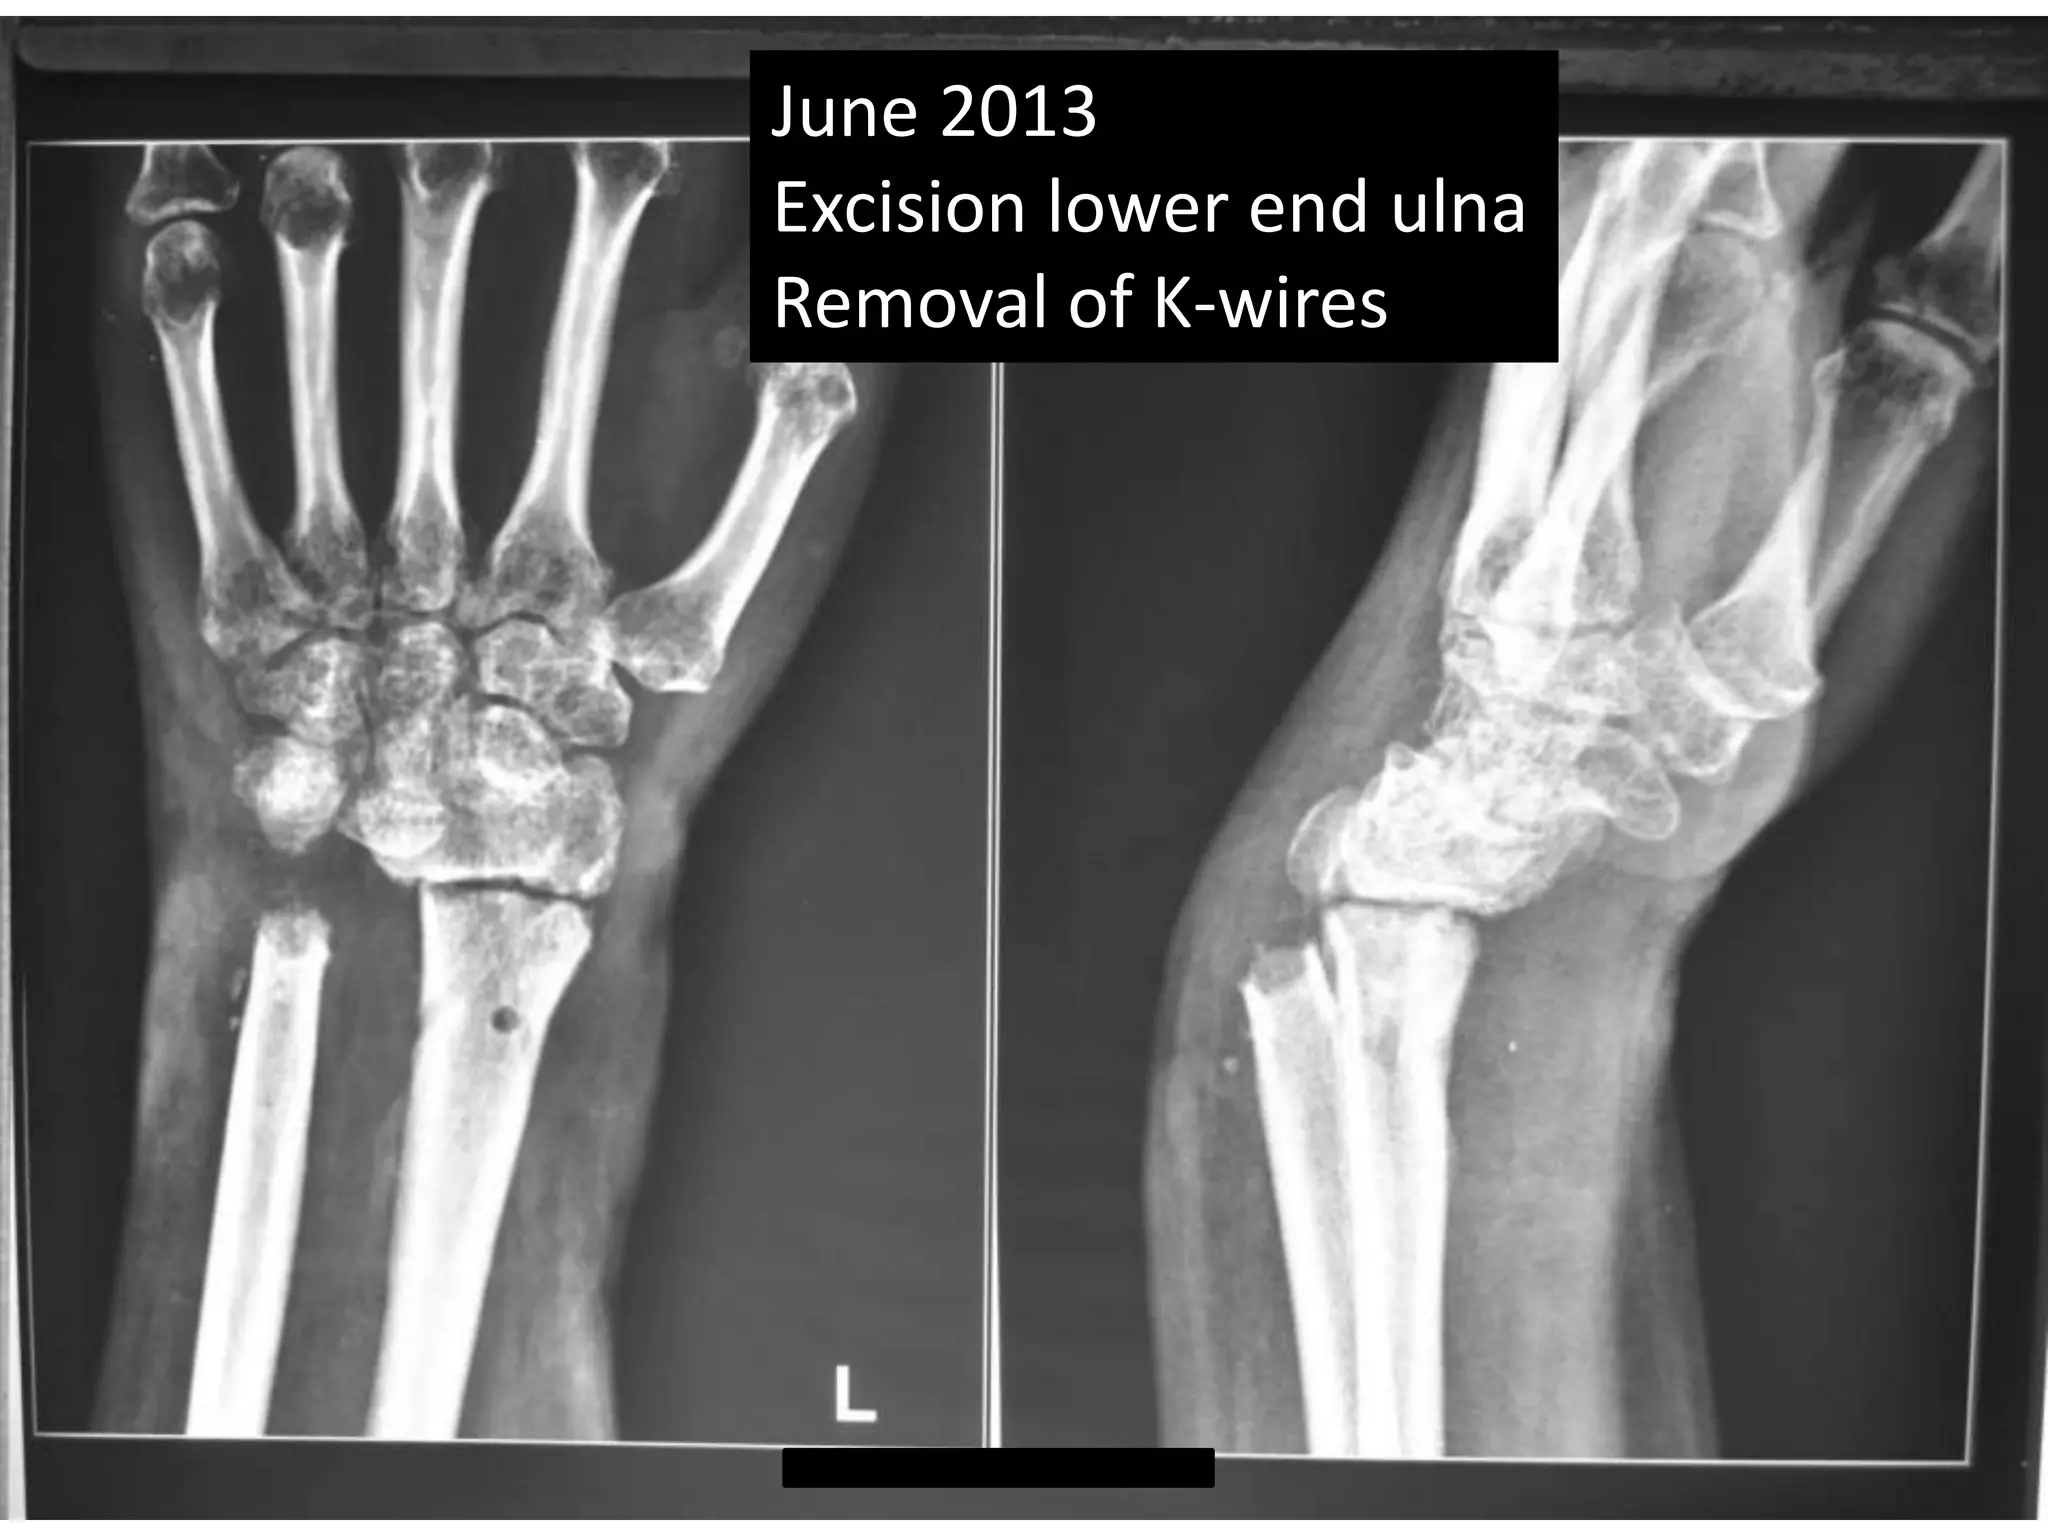

June 2013

Excision lower end ulna

Removal of K-wires

June 2013 Excisionlower end ulna Removal of K-wires